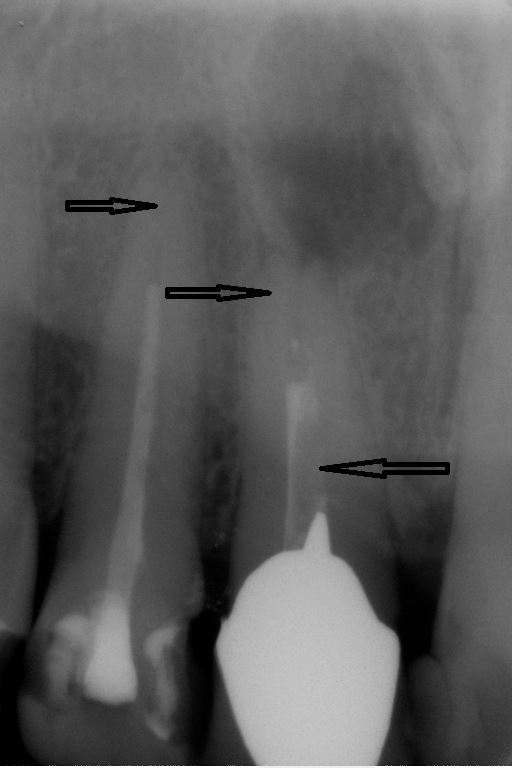

Fallbeispiel für eine unvollständige Wurzelfüllung

nach Revision und dichtem Verschluss

Im ersten Schritt wird nach der Eröffnung des Zahnes die alte Wurzelfüllung entfernt und es erfolgt die Reinigung des gesamten Systems. Nach dem Reinigen wird für einige Zeit ein desinfizierend und gewebsauflösendes Medikament in den Zahn eingebracht, welches die Desinfektion auch in schwierig erreichbaren Nebenbereichen des Kanalsystems unterstützt.

Sind Reinigung und Desinfektion des Zahnes abgeschlossen, werden die sauberen Kanäle mit der thermoplastischen Obturation 3-dimensional verschlossen. Auch die kleinen Seitenkanäle können so verschlossen werden.